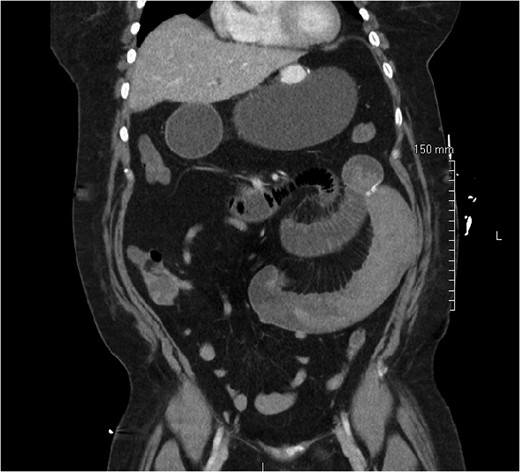

On post-operative day 1, she complained of nausea, vomiting and abdominal pain, though symptoms were consistent with an expected post-operative course. On post-operative day 2, however, she developed a leukocytosis of 15 600/mm3 and an intermittent tachycardia ranging from 85 to 118 bpm. An abdominal CT was obtained, which demonstrated a SBO with a transition point distal to the jejunojejunostomy anastomosis (Fig. 1). The patient was taken to the operating room for diagnostic laparoscopy. Upon initial inspection, there was no evidence of a mechanical cause for obstruction such as kinking or adhesions. However, the bowel proximal to the common channel appeared dilated and discolored (Fig. 2). Esophagogastroduodenoscopy (EGD) was performed to inspect the luminal mucosa, which was pink and well-perfused. Inspection distal to the jejunojejunostomy revealed a 50 cm section of bowel that was firm and appeared to be the point of obstruction. An enterotomy was made in the proximal common channel, which revealed a large intraluminal clot (Fig. 3). This was removed piecewise with a combination of suction and manual extraction (Fig. 4). There was no evidence of active bleeding or leakage from the jejunojejunostomy anastomosis. Due to the friability of the intestinal walls and absence of active bleeding, the anastomosis was not revised and the enterotomy was primarily closed.

Intraluminal clot within the common channel after an enterotomy was created.